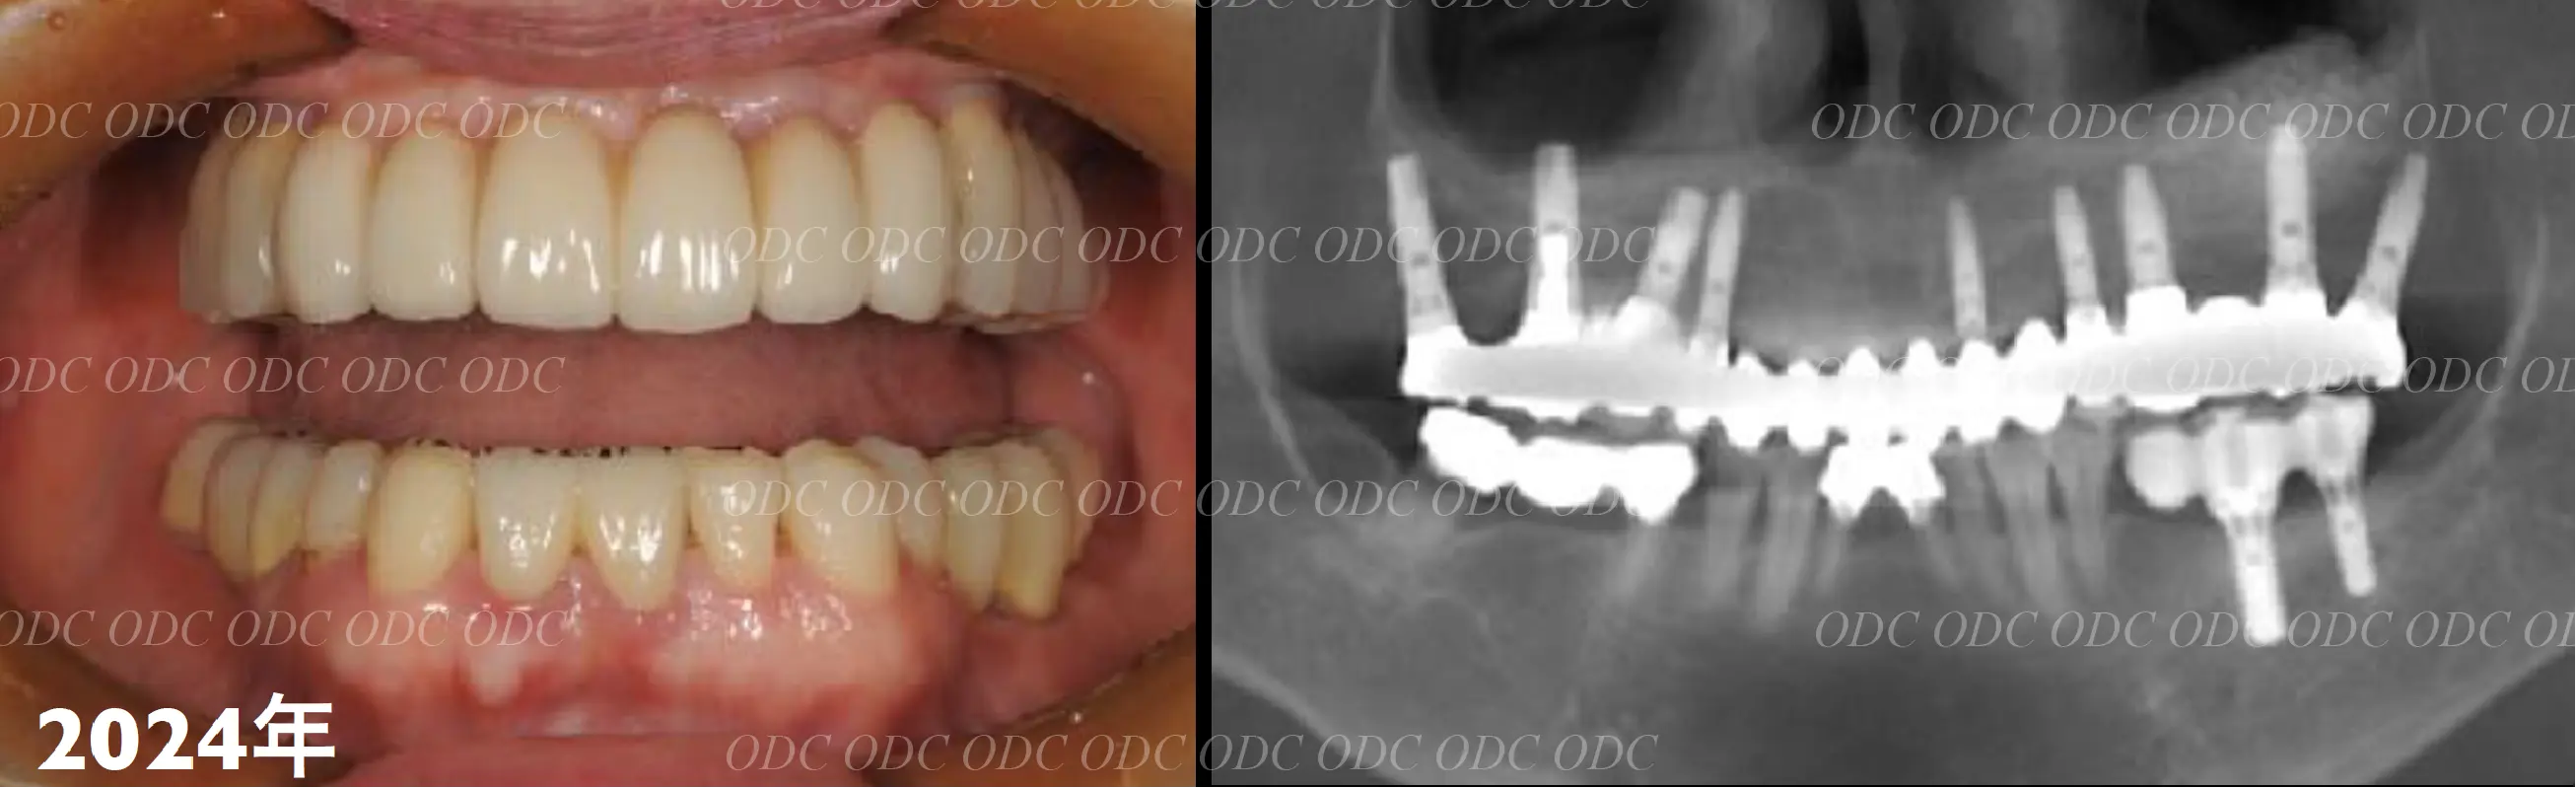

2024年、治療終了後約10年が経過いたしました。

顎関節を考慮した包括的な治療を行うことで咬合状態(噛み合わせ)は現在もとても安定した状態です。